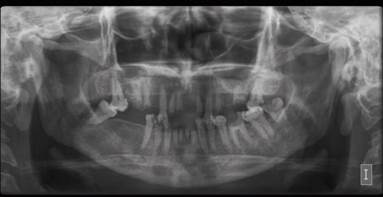

A 25-year-old patient attended presenting a bilateral and painful submandibular, sublingual and submental swelling with 3 days of evolution, associated with dyspnea, dysphagia, and odynophagia. His medical record was remarkable for an uncontrolled type I DM (this for socioeconomic reasons; the patient was not taking insulin therapy on a regular basis). Intraorally, multiple bilateral radicular rests associated with purulent discharge were observed (Figure 1), leading to the diagnosis of LA and thus, hospital admission was decided for a multidisciplinary management along with the internal medicine service. Insulin therapy and fluid-therapy along with an empirical IV triple antibiotic therapy was immediately started (vancomycin, ampicillin + sulbactam, and clindamycin) until culture results could be obtained. Within the first 24 hours of intrahospital stay, the status of the patient worsened: signs of sepsis were observed and the swelling extended to the infraclavicular area bilaterally. Also, areas of NF appeared in the submandibular and submental regions (Figure 2). Hence, on a first surgical intervention under general anesthesia, a surgical drainage along with debridement of the necrotic areas and extraction of the non-vital teeth was performed. The excised tissue was sent for histopathological analysis, confirming the diagnosis of NF and ruling out other entities like mucormycosis. A culture of the drained secretion was processed, revealing a moderate amount of bacillius spp sensitive to meropenem. After the intervention, the patient was immediately translated to the ICU and his status had a mild improvement.